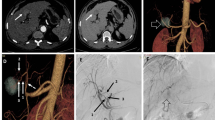

The hepatic arterial segmental vascularization patterns are summarized in Table 4 and schematically illustrated in Figs. 2, 3, 4, 5 and 6. An example of DSA and multiplanar MDCT images of the hepatic arterial segmental vascularization pattern is shown in Fig. 7 for a patient with an rRHA originating from the SMA.

DSA (A–B) and multiplanar MDCT (C–F) images of the hepatic arterial segmental vascularization pattern in a patient with an rRHA originating from the SMA. A Superior mesenteric arteriogram shows a replaced right hepatic artery (white arrowhead) originating from the SMA. B DSA obtained from the CHA. The CHA divides into GDA and LHA (black asterisk). The LHA first gives of a branch to S2 (black arrowhead), and bifurcates more distally into a branch to S3 (white arrow) and S4 (black arrow). C–D Corresponding arterial phase coronal MIP images. E–F Corresponding arterial phase axial MIP images. Note the retroportal course of the rRHA (white arrowhead), and the perfect intrahepatic coordination between distal portal and arterial branches